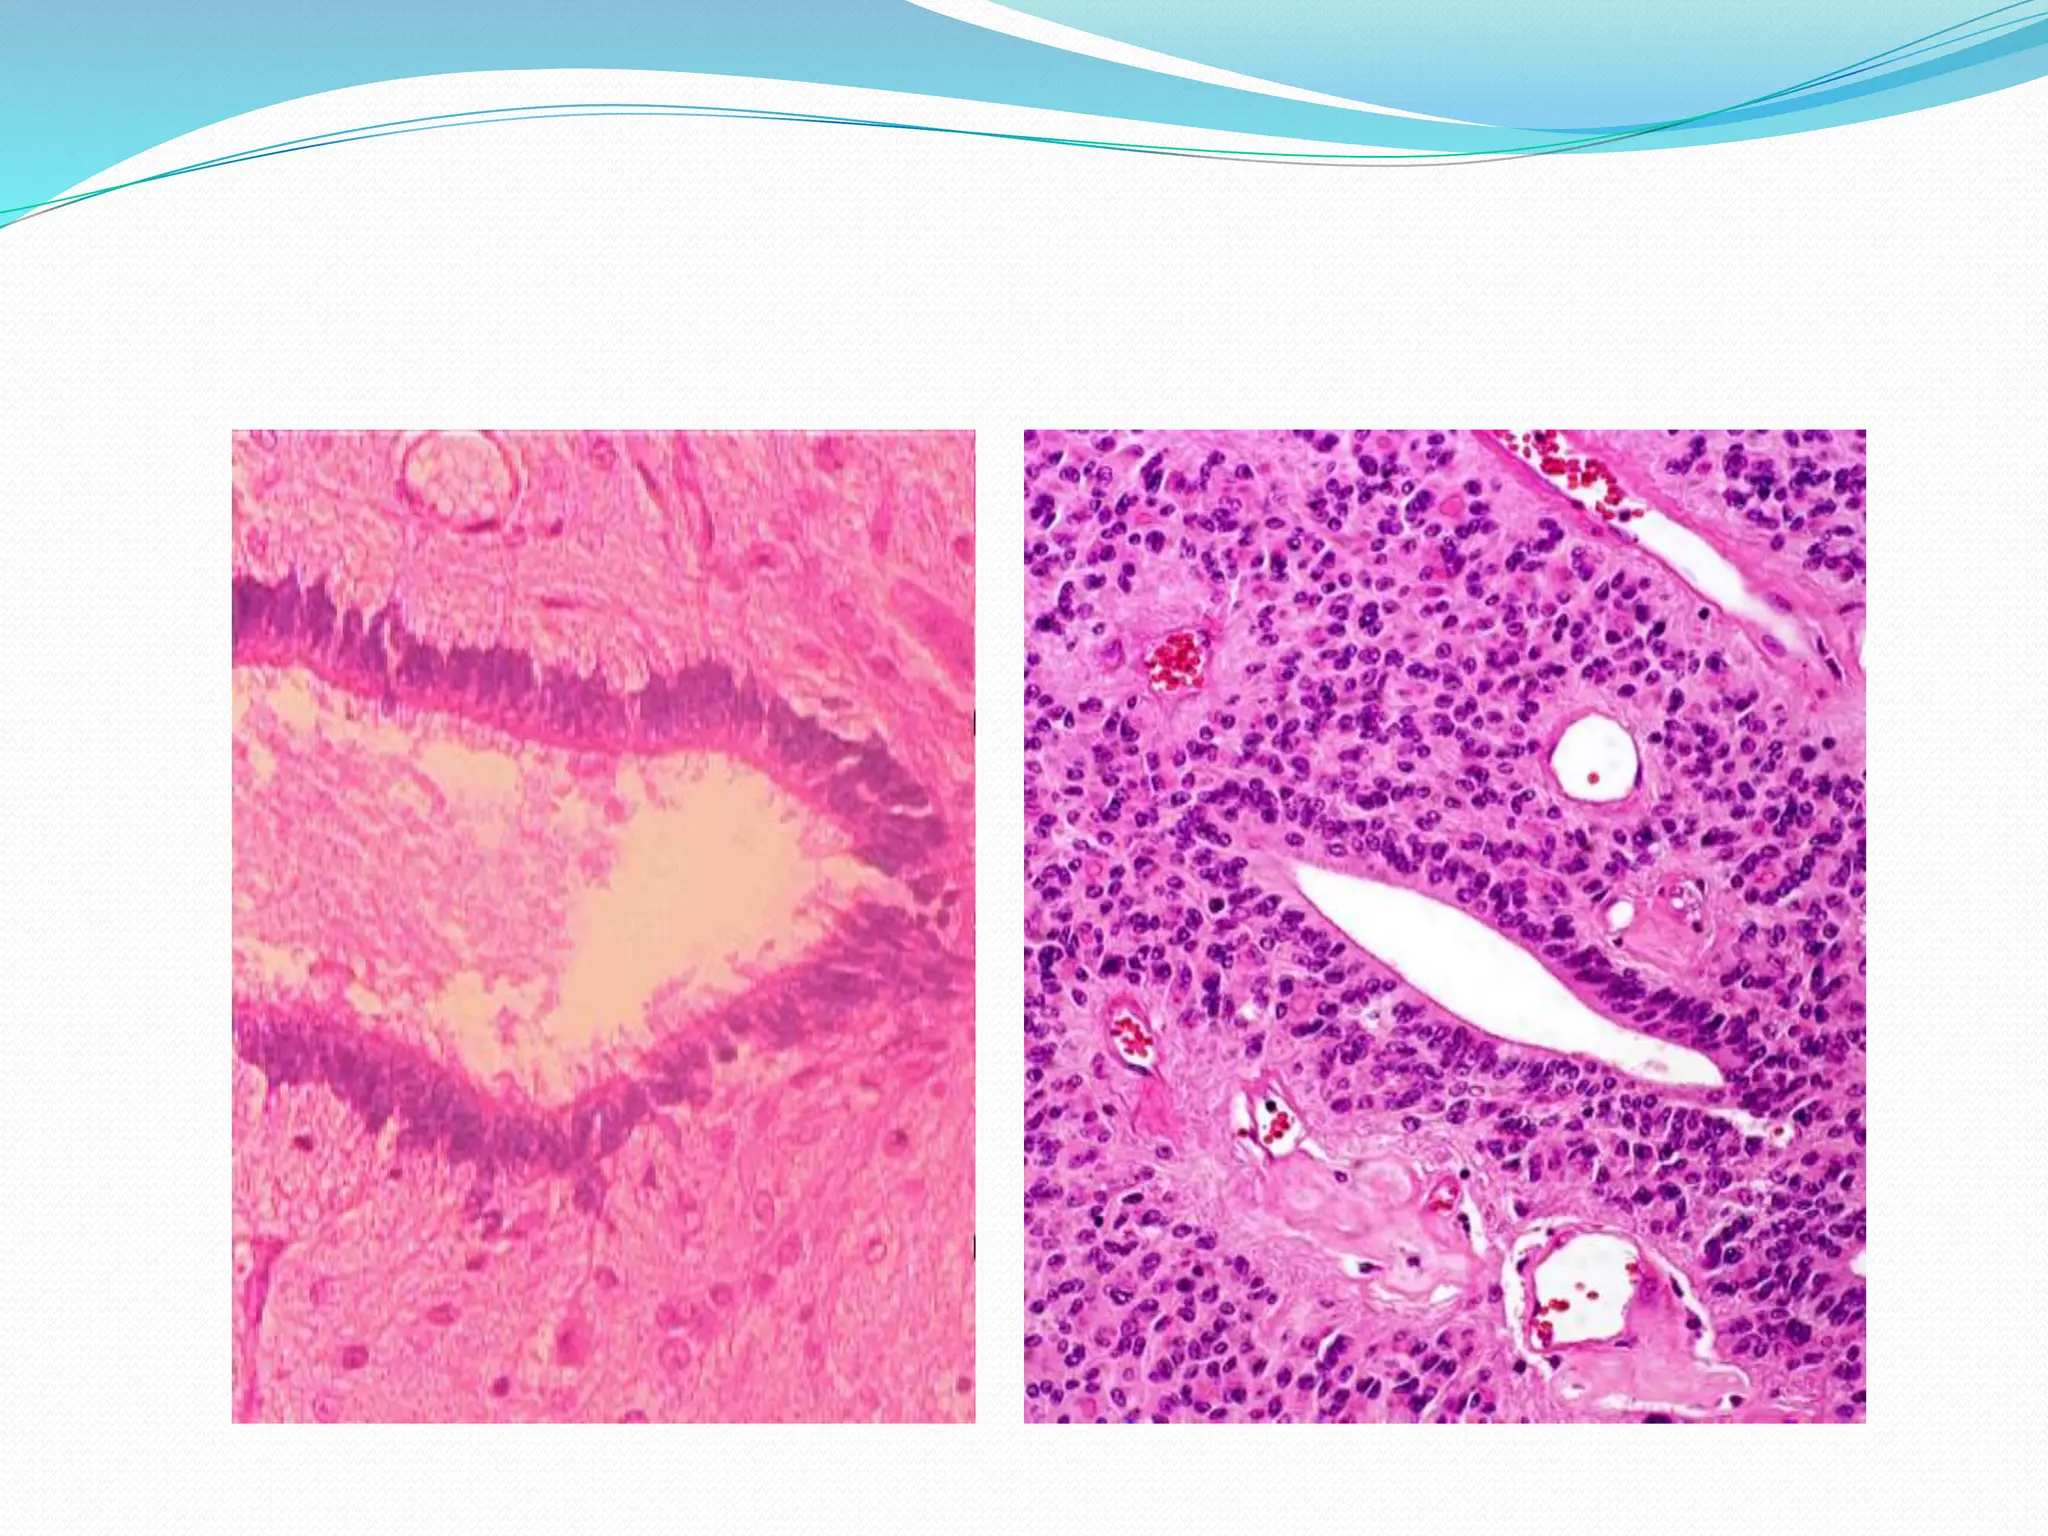

SCHWANNOMA

Microscopy:

 Mixture of 2 growth patterns of elongated cells

with regular, oval nuclei & cytoplasmic processes.

 Antoni A pattern:

 moderate to high cellularity ,

 cells arranged as fascicles,

 little stromal matrix.

 nuclear free zones of cytoplasmic processes that

lie between nuclear palisading  ‘verocay bodies’

 Antoni B pattern: hypocellular, loose meshwork

of cells with microcysts, myxoid areas

ANTONI A WITH

VEROCAY BODIES ANTONI B

NEUROFIBROMA

 Skin: cutaneous NF

 Peripheral nerve: solitary NF

 Arise sporadically or with NF1 plexiform NF

 Cutaneous – nodules , in dermis & fat,

as well demarcated, but unencapsulated masses

of spindle cells, highly collagenised stroma

 Plexiform: large nerve trunk, multiple, nerve

irregularly expanded.

 lesions cannot be separated from nerve,

 Microscopy: loose myxoid background, low

cellularity.

 Schwann cells - Elongated nuclei, extension of pink

cytoplasm

 Large, multipolar fibroblasts

 Inflammatory cells.

 Collagen bundles in the background of myxoid

areas look as shredded carrot

Microscopy:  Mixture of2 growth patterns of elongated cells with regular, oval nuclei & cytoplasmic processes.  Antoni A pattern:  moderate to high cellularity ,  cells arranged as fascicles,  little stromal matrix.  nuclear free zones of cytoplasmic processes that lie between nuclear palisading  ‘verocay bodies’  Antoni B pattern: hypocellular, loose meshwork of cells with microcysts, myxoid areas

ANTONI A WITH VEROCAYBODIES ANTONI B

NEUROFIBROMA  Skin: cutaneousNF  Peripheral nerve: solitary NF  Arise sporadically or with NF1 plexiform NF  Cutaneous – nodules , in dermis & fat, as well demarcated, but unencapsulated masses of spindle cells, highly collagenised stroma  Plexiform: large nerve trunk, multiple, nerve irregularly expanded.  lesions cannot be separated from nerve,

 Microscopy: loosemyxoid background, low cellularity.  Schwann cells - Elongated nuclei, extension of pink cytoplasm  Large, multipolar fibroblasts  Inflammatory cells.  Collagen bundles in the background of myxoid areas look as shredded carrot  Malignant transformation high for plexiform NF as MPNST